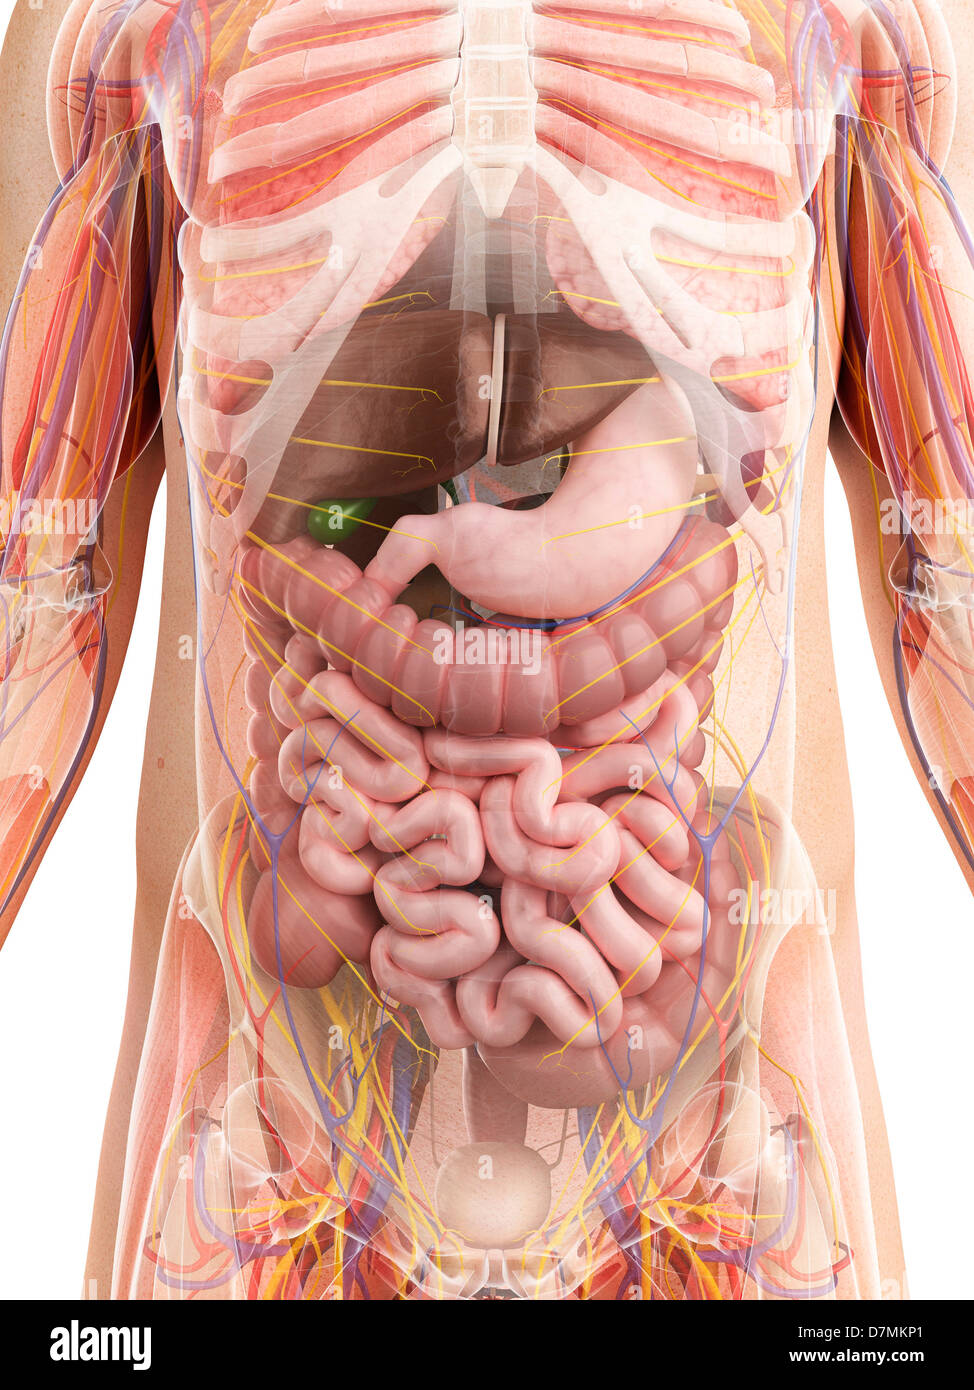

RFDGYRD7–Männliche Anatomie, inneren Organe allein, volle Atmungs- und Verdauungssystem, mit einigen Organen Cutaway. Anatomie-Bild.

RF2GB8D4J–3D-Darstellung des Verdauungssystems der männlichen Anatomie, zusammen mit anderen inneren Organen. Glasbild auf blauem Hintergrund, Vorderansicht.